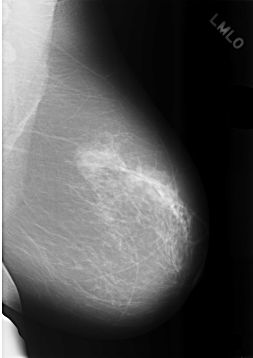

C_0479_1.LEFT_MLO

LEFT_MLO LINES 5728 PIXELS_PER_LINE 4048 BITS_PER_PIXEL 12 RESOLUTION 50 NON_OVERLAY